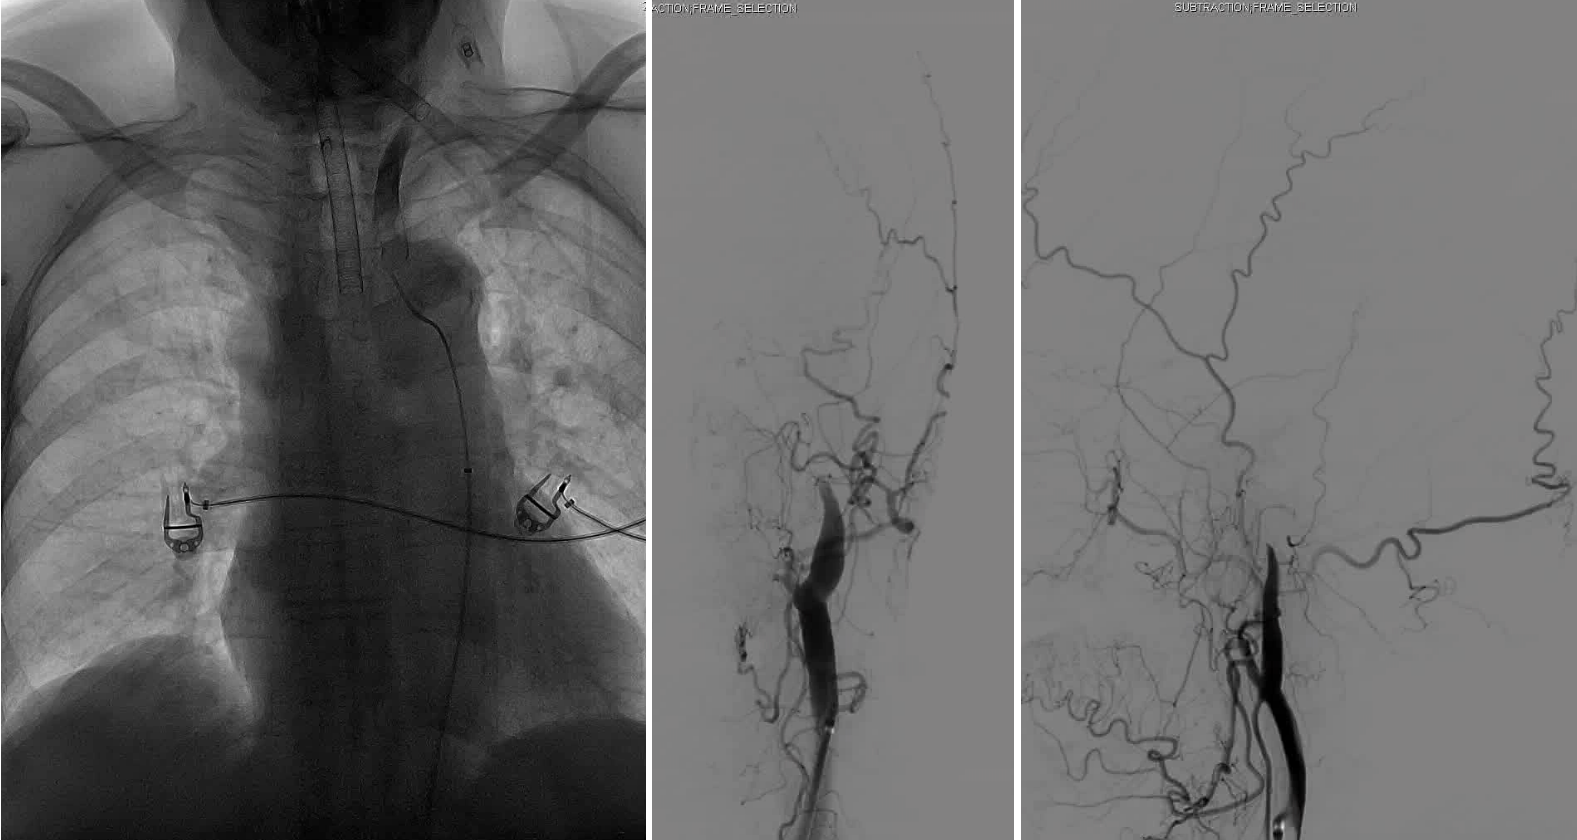

DSA显示ICAO

微导管造影证实MCAO

手术过程

中间导管配合在长鞘和小球囊的配合下穿过迂曲夹层的颈内动脉。

微导管微导丝越过MCA闭塞段,置入取栓支架支架。

微导管微导丝穿过夹层段,4.0×20mm球囊再次反复贴附夹层段,促进内膜贴壁。

造影观察,管腔狭窄较前好转,血流状态稳定,结束手术。